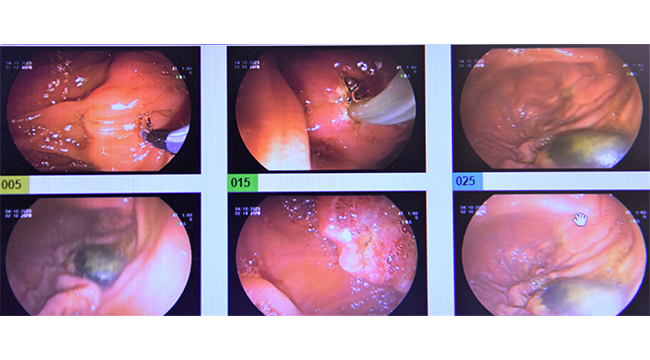

Bir süredir mide ve sırt ağısı şikayeti ile ağrı çeken 74 yaşındaki kadın hastanın safra kesesinden 1 cm büyüklüğünde 14 mm çapında yaklaşık olarak bıldırcın yumurtası büyüklüğünde taş çıktı. ERCP yöntemiyle safra yollarından çıkarılan taş sonrasında hasta kısa sürede sağlığına kavuştu.

İşlemi gerçekleştiren Genel Cerrahi Uzmanı Op. Dr. Uğur Kahan Öztürk , safra kesesindeki taşların alınmasında kullanılan safra yolunun endoskopik tedavisi (ERCP) yöntemi hakkında bilgi verdi. Dr. Öztürk “ Safra kesesinde oluşan taşlar, hastanın hayat kalitesini olumsuz etkilediği gibi safra yollarını tıkayabilme riski nedeniyle yaşamsal önem taşıyor. Özellikle yemeklerin sindiriminde önemli bir görevi bulunan safra yolundaki taşları endoskopik tedavi (ERCP) yöntemiyle ameliyatsız olarak alabiliyoruz. Yapılan işlem sonrasında da hastamız kısa sürede eski hayatına geri dönebilir.” dedi.